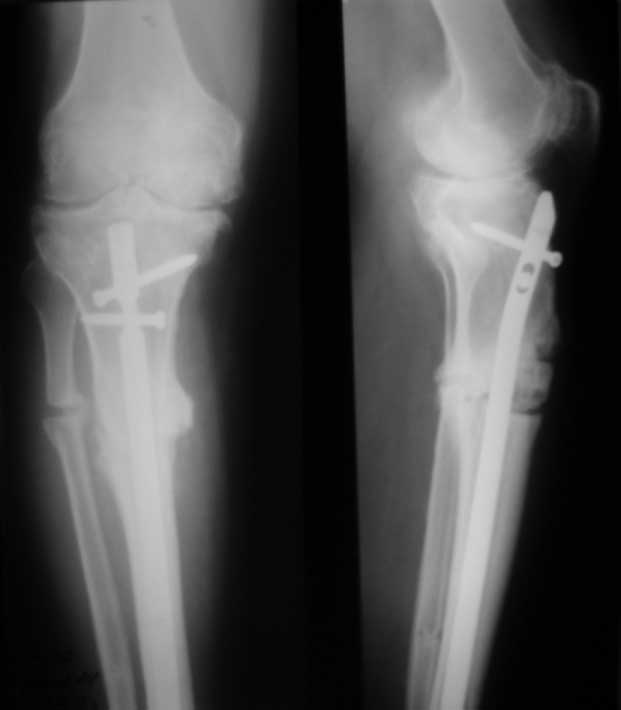

У пациента 50 лет имеется разгибательная контрактура через 8 меспосле ТКА. Уважаемые коллеги. Пациент 8 мес после операции ТКА, в анамнезе – неправильно сросшийся перелом голени, коррекция оси (снимки прилагаются. В настоящее время имеется разгибательная контрактура 10/5/0, на операционном столе было 90/0/5, на момент выписки движения 50/0/0 в надежде на дальнейшую разработку. До эндопротезирования 40/10/0. Глубокая инфекция исключена. Ротация бедренного компонента в норме (по КТ). Вопросы: насколько для такого ограничения критична некорректная установка б/б компонента (я намерял 7 град)? Причина нынешнего состояния, артрофиброз? Какие действия следует предпринять, удаление рубцов, релиз головок 4-главой мышцы? Что-либо другое, ваше мнение? С уважением, Максим Агалаков, Екатеринбург.

Низковат, соласен. Соориентируетесь при операции, если ограничивает движения, перенести бугристость или Z-образная тенотомия связки надколенника, артросокпический артролиз обязательно.